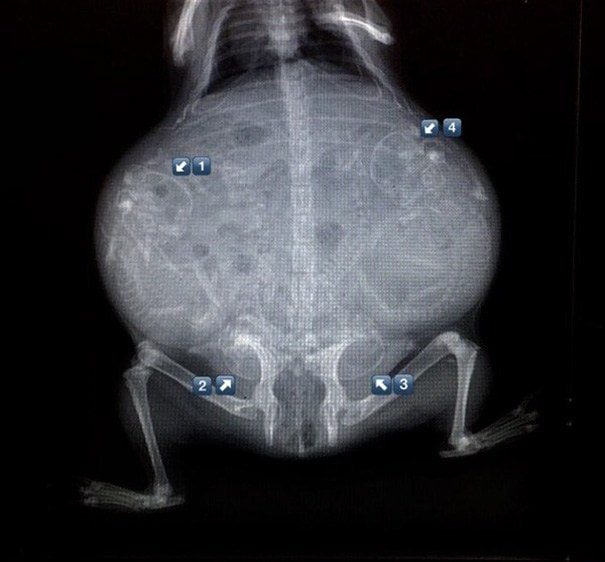

Беременная морская свинка